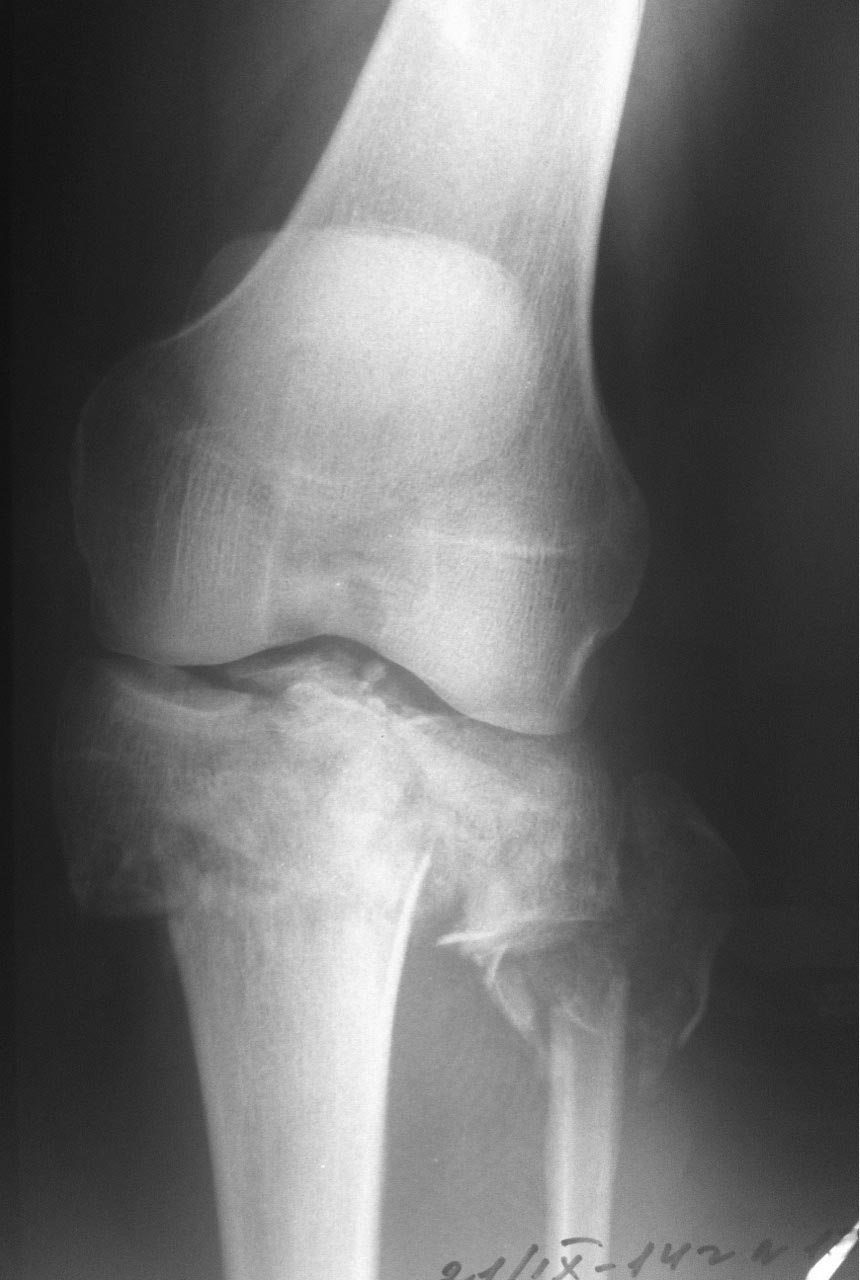

Вот и вторая проекция.